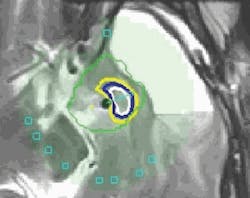

FIGURE 4. This software output graphic, generated by VizApp, shows the minimum (outlined in yellow) and maximum (outlined in white) generated iso-dosage regions that guided the surgeon during laser therapy application. Positioning of the side-firing probe is indicated in turquoise, while the center arrow depicts the direction of the laser energy.

In clinical investigations, once the laser had been activated inside the target tissue, the software first displayed a yellow thermal iso-dose line on the MRI image (see Fig. 4). All cells within the yellow iso-dose line had been exposed to the thermal dosage demonstrated to have a detectable effect–which, depending on many factors, could range from a nonphysiological effect (most likely) to cell death (very unlikely). All tissue outside of this yellow boundary line had been demonstrated in animal studies to experience no irreversible changes or damage. As the laser energy continued to be delivered, a blue iso-dose line appeared. The blue boundary indicates tissue that had been exposed to the thermal equivalent that was expected, again based on prior results, to cause significant damage and necrosis within two days, depending on multiple physiological factors. The final thermal iso-dose line to emerge was white, indicating the boundary of tissue that had been exposed to the thermal dosage previously shown to cause near-immediate tissue death. Typical laser energy applications were <5 min, depending on the size and geometry of the tumor. Multiple applications of laser energy were necessary at different angles and levels. Following a LITT treatment, the treated target mass eventually shrinks in volume, presumably as tissue is resorbed through natural processes.